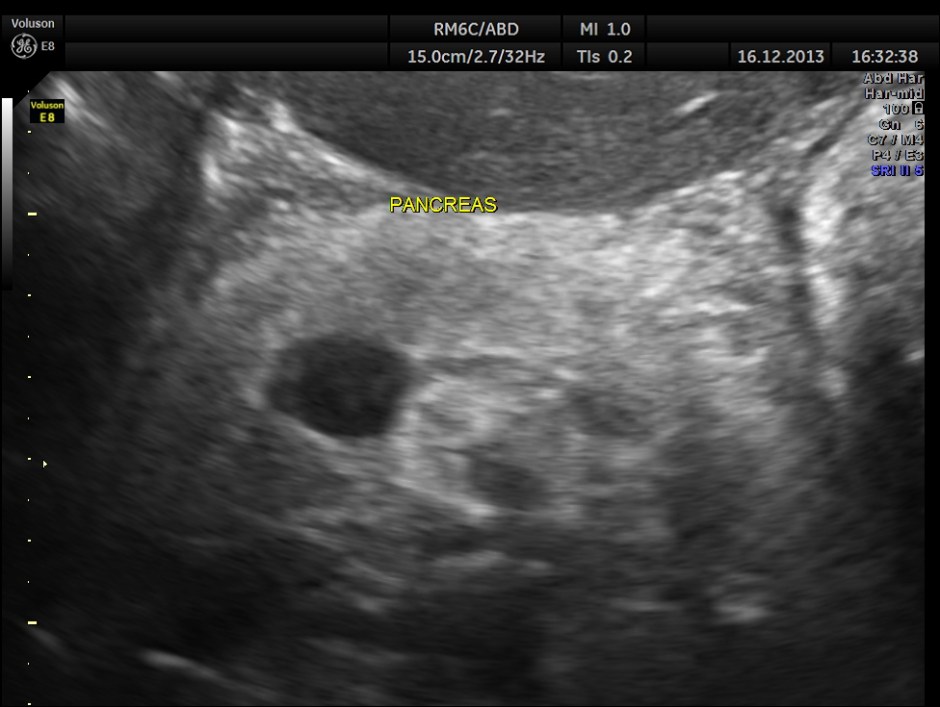

The pancreas appeared to be normal.